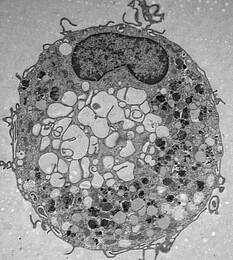

Les thèmes principaux d’EURIdoc sont l’hématopoïèse, le développement du système immunitaire, l’immunité innée et adaptative ainsi que certaines maladies immunitaires. Le projet porte également sur le problème immunologique le plus urgent de notre époque, la Covid-19, et prévoit, entre autres, de développer de nouvelles thérapies contre le SARS-CoV-2. La coopération allant au-delà du secteur universitaire avec quatre hôpitaux et dix partenaires industriels est à cet égard une base importante. Les doctorantes et doctorants auront ainsi la possibilité d’effectuer des séjours de recherche dans des entreprises pharmaceutiques de premier plan aussi bien que dans des entreprises de petite et moyenne taille et dans des laboratoires académiques.